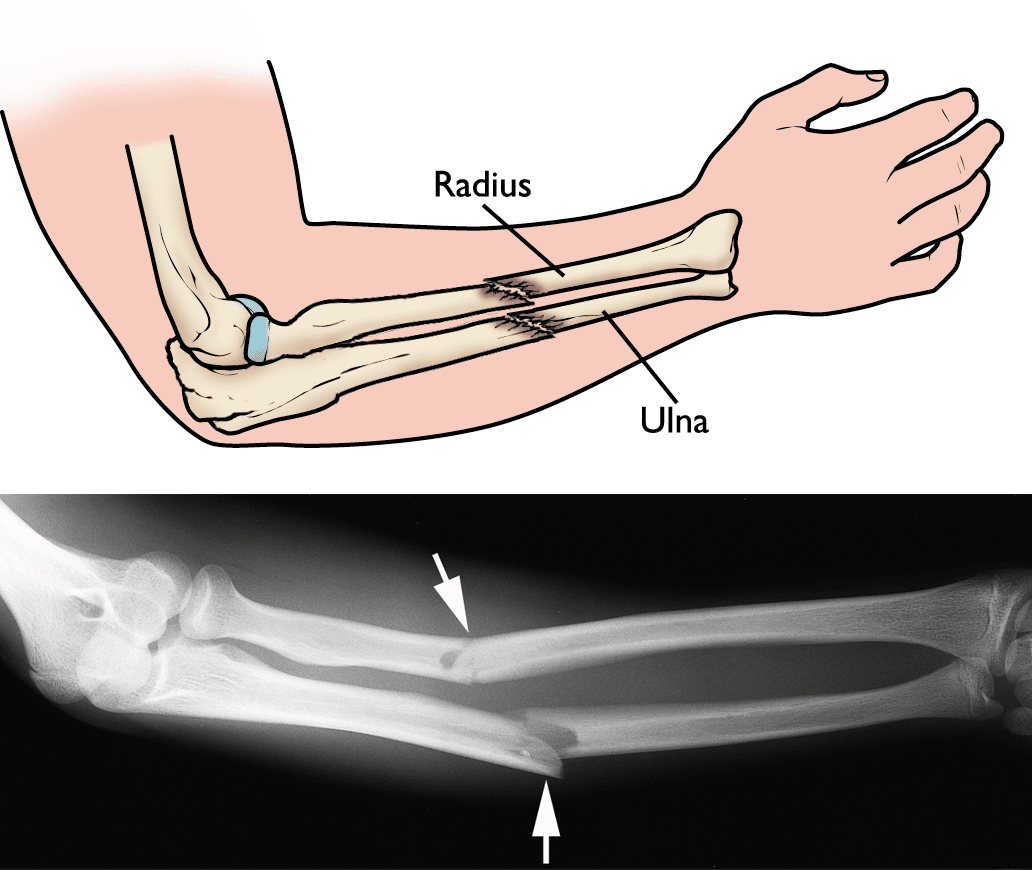

The radius is one of two bones in your forearm. When holding your hands out in front of you with palms up, the radius is the bone on the outside or on the side your thumb is pointing to. This bone may break from falling on an outstretched hand or from blunt force trauma. Fractures of the radius can occur at the wrist, the elbow or in the middle. This article will focus on the middle segment. The radius plays a role in forearm rotation, so any fracture to this bone will affect your ability to rotate your arm and bend/straighten your wrist and elbow.

As previously mentioned, radius fractures usually occur when you fall on an outstretched arm or when you receive a direct blow to your forearm. There are different ways the bone can break. The bone can slightly crack or break into many pieces. If the bone breaks into a number of fragments, the pieces can still be aligned in their normal positions or be far out of place (displaced fracture). Sometimes, bone fragments can stick out through the skin (open fracture), which is very serious and requires immediate medical attention.